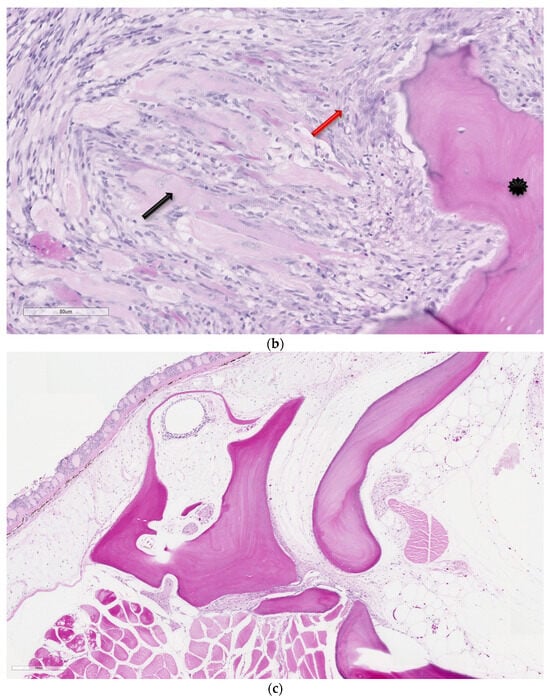

Figure 2.

(a,b). Dysgerminoma from a chub. The neoplasm is comprised of sheets of dysplastic oogonia (indicated with a red arrow), displaced by occasional interstitium (indicated with a black arrow). Hematoxylin and eosin. (c,d) Normal control histology of a stage 1 (early development) ovary in a chub (oogonia indicated with a black arrow). Hematoxylin and eosin.